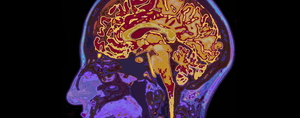

뇌졸중 발생 6개월 이후라도 뇌 구조가 재편돼 상지 운동 기능이 회복될 수 있는 것으로 확인됐다. 가톨릭대 성빈센트병원 재활의학과 유연지 교수팀은 뇌졸중 경험 만성기 환자를 대상으로 대뇌 및 소뇌의 구조적 변화와 상지 운동 기능의 관련성을 분석해 뇌졸중분야 국제학술지(Stroke)에 발표했다.만성기란 병의 진행이 멈췄거나 더디게 진행 중이지만 장기적인 관리, 재활, 돌봄이 필요한 상태를 말한다.뇌졸중 후 신경 회복과 재활 효과는 주로 발병 후 3~6개월 이내인 급성기 및 아급성기에 많이 나타난다고 알려져 있어, 만성기 환자는 재활

두개골이 손상됐어도 경두개직류자극술(transcranial Direct Current Stimulation, tDCS)이 가능한 것으로 확인됐다.신경조절치료법인 tDCS는 두피에 전극을 부착해 전류 저항성이 높은 두개골을 통과하면서 분산돼 원하는 부위에 자극을 도달시키는 방식이다. 하지만 두개골이 손상되면 해당 부위의 흐름이 달라져 치료 목표점이 아닌 다른 부위에 영향을 미칠 우려가 있었다.이런 가운데 가톨릭의대 재활의학과 서울성모병원 임성훈 (공동교신저자), 성빈센트병원 윤미정(제1저자) 교수팀과 인공지능 기술 기반 뇌질환 솔루션

뇌손상 환자에 대한 뇌신경조절 치료시 인공지능(AI)으로 효과를 높일 수 있다는 연구결과가 나왔다.가톨릭대 성빈센트병원 재활의학과 임성훈‧유연지‧윤미정 교수와 부천성모병원 재활의학과 임선‧박혜연 교수, 서울성모병원 재활의학과 박혜정 교수는 AI 기반의 뇌 분할 분석법을 적용한 개인 맞춤형 경두개 직류자극 치료(tDCS)의 효과를 제5회 국제 뇌 자극 컨퍼런스(5th International Brain Stimulation Conference)에서 발표했다.tDCS는 두피 위에 위치한 전극을 통해 뇌 표면에 약한 직류자극을 보내 신경